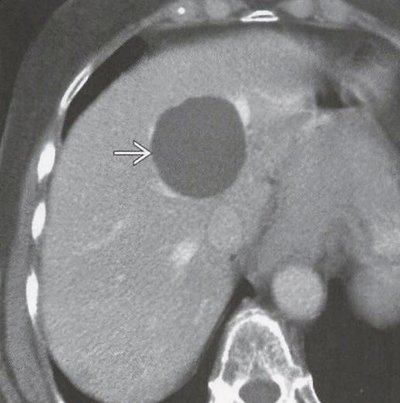

肝海绵状血管瘤的影像诊断

图 影像诊断报告(肝海绵状血管瘤)

进一步行腹部增强ct检查后,确诊为肝脏海绵状血管瘤,大小约6

目前,影像学检查(如b超,ct,mri)是诊断肝血管瘤的主要方法